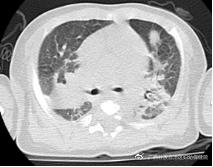

经过22天的奋战,患儿肺部团块影减少,呼吸机顺利撤离,避免了严重并发症的发生。经过46天的治疗,患儿得以顺利出院。患儿基因回报为:慢性肉芽肿病。

治疗后